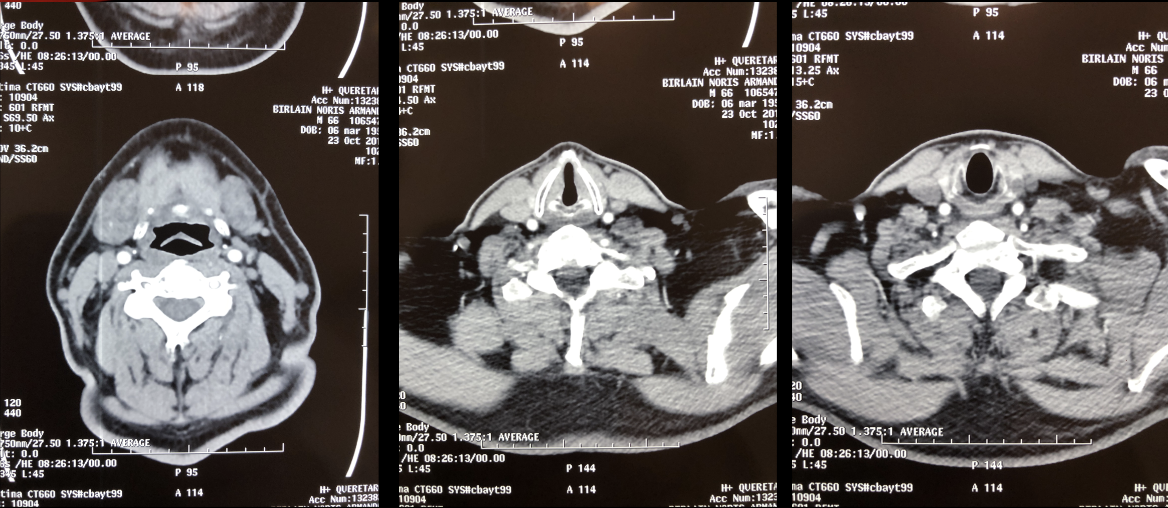

Foto de enmedio: forma de casa: luz glótica y cartílago tiroides que puede tener forma de lágrima o forma de reloj de arena.

Subglutis 3era foto huevito

TAC / AXIAL

NIVEL GLÓTICO:

CUERDAS VOCALES

Y CARTÍLAGO

TIROIDES